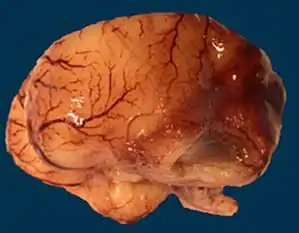

Microlissencephaly in a 27 WG (week of gestation) foetus with TUBB2B mutation. Macroscopical view of the left hemisphere showing agyria, absent sylvian fissure and absent olfactory bulb.

Microlissencepahly is considered a tubulinopathy (tubulin gene defect)[30] i.e. is caused by mutation in tubulin genes, mainly TUBA1A[31] and less commonly TUBB2B, TUBB3, TUBA3E and TUBG1.[32] Central pachygyria, polymicrogyria are more commonly seen in patients with defects in TUBB2B, TUBB3, and TUBB5.[33] This implys the critical role of microtubule cytoskeleton in the pathophysiology of microlissencephaly as well as other neuronal migration disorders.[20]